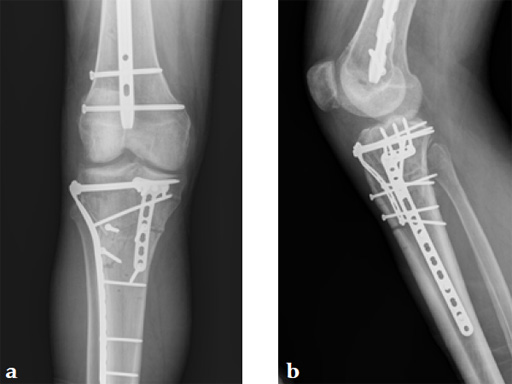

Staged management with initial rodding of femur and placement of spanning knee external fixator with closed manipulative reduction of tibial plateau (Fig 3).

The patient returned to the operating room once soft tissue allowed for open reduction and internal fixation of the tibial plateau fracture via a lateral utility and anteromedial approach. Placement of low bend 3.5 mm proximal tibia plate laterally and 3.5 mm locking T-plate anteromedially to buttress the impacted anterior rim (Fig 4, Fig 5).